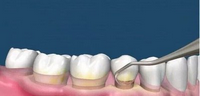

牙周发炎引起的牙齿松动应及早就诊,可以到专业的口腔医院通过洗牙,减轻齿牙周边的炎症发生和加重,缓和牙槽骨被吸收,但需要重复多次。